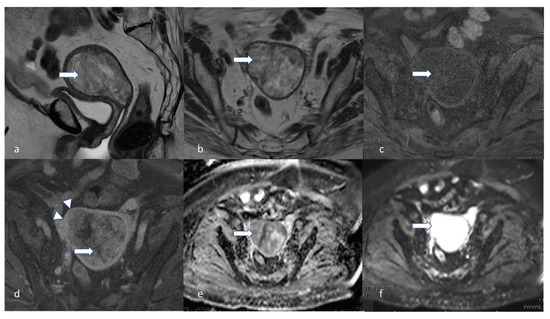

5.3. Magnetic Resonance Imaging (MRI)

- Maheshwari, E.; Nougaret, S.; Stein, E.B.; Rauch, G.M.; Hwang, K.-P.; Stafford, R.J.; Klopp, A.H.; Soliman, P.T.; Maturen, K.E.; Rockall, A.G.; et al. Update on MRI in Evaluation and Treatment of Endometrial Cancer. RadioGraphics 2022, 42, 2112–2130. [Google Scholar] [CrossRef] [PubMed]

- Nougaret, S.; Reinhold, C.; Alsharif, S.S.; Addley, H.; Arceneau, J.; Molinari, N.; Guiu, B.; Sala, E. Endometrial Cancer: Combined MR Volumetry and Diffusion-weighted Imaging for Assessment of Myometrial and Lymphovascular Invasion and Tumor Grade. Radiology 2015, 276, 797–808. [Google Scholar] [CrossRef]

- Soneji, N.D.; Bharwani, N.; Ferri, A.; Stewart, V.; Rockall, A. Pre-operative MRI staging of endometrial cancer in a multicentre cancer network: Can we match single centre study results? Eur. Radiol. 2018, 28, 4725–4734. [Google Scholar] [CrossRef]

- Bi, Q.; Bi, G.; Wang, J.; Zhang, J.; Li, H.; Gong, X.; Ren, L.; Wu, K. Diagnostic Accuracy of MRI for Detecting Cervical Invasion in Patients with Endometrial Carcinoma: A Meta-Analysis. J. Cancer 2021, 12, 754–764. [Google Scholar] [CrossRef]

- Nougaret, S.; Horta, M.; Sala, E.; Lakhman, Y.; Thomassin-Naggara, I.; Kido, A.; Masselli, G.; Bharwani, N.; Sadowski, E.; Ertmer, A.; et al. Endometrial Cancer MRI staging: Updated Guidelines of the European Society of Urogenital Radiology. Eur. Radiol. 2019, 29, 792–805. [Google Scholar] [CrossRef]